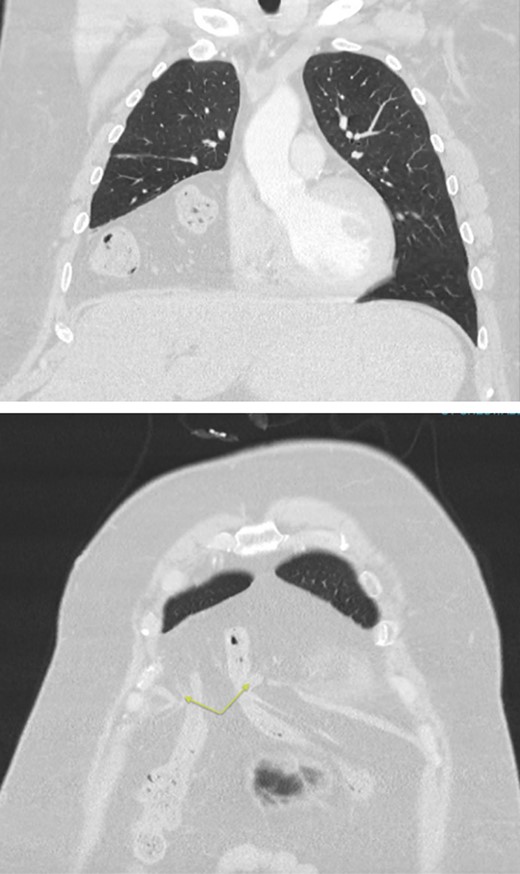

A chest x-ray and subsequent CT showed a large right anterior diaphragmatic hernia through the foramen of Morgagni, with colon in the chest, occupying about two-thirds of the pleural space (Fig. 1). Radiologically the defect measured 39 mm in AP dimension and 38 mm transverse. As the patient was asymptomatic from the hernia, the decision was made to undertake the hernia repair electively at a later time.

CT chest/abdomen/pelvis with large volume Morgagni hernia containing loops of bowel in the right hemithorax. Arrows highlighting the diaphragmatic defect.